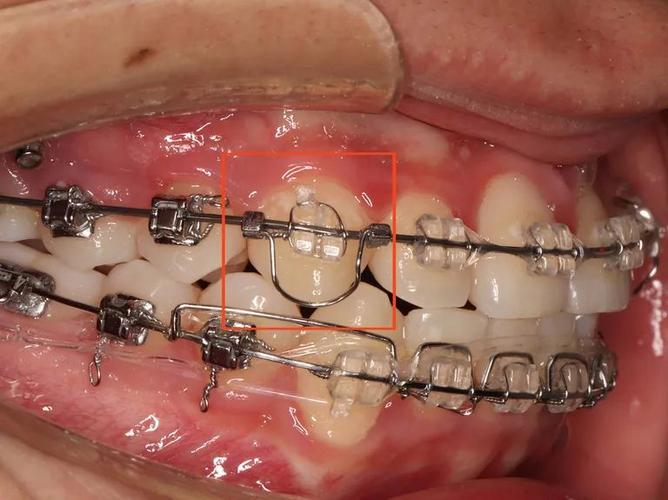

压低辅弓的核心在于通过弓丝的形变产生持续、轻柔的压低力,同时避免牙齿发生不必要的倾斜或旋转,其结构通常包括主弓丝和辅弓两部分:主弓丝(如不锈钢丝或β钛丝)提供基础支抗,辅弓(多为镍钛丝或澳丝)通过特定的弯曲形态(如“Ω”形曲、垂直曲)与托槽或附件连接,当辅弓被激活后,产生的力量通过托槽传递至牙冠,作用于牙槽骨,引导牙槽骨改建,实现牙齿压低。

力学控制是关键:辅弓的设计需确保力量中心位于牙根长轴附近,避免产生过大的力矩导致牙齿倾斜,针对前牙压低,辅弓常在侧切牙远中弯制停止曲,配合牵引钩与颌骨或后牙支抗装置连接,形成“压低-支抗”平衡系统;而后牙压低则需辅弓与磨牙带环或种植支抗钉协同,通过后牙垂直向移动为前牙压低提供空间。

- 形态设计:前牙压低辅弓常呈“”形,在侧切牙远中弯制垂直曲,配合牵引钩与颌骨或腭杆连接;后牙压低辅弓则需在磨牙区弯制后倾曲,与磨牙带环或种植钉形成锚固。

粘接附件与施力

- 附件粘接:目标牙需粘接标准方丝弓托槽或专用压低托槽,确保托槽高度和位置准确(如前牙托槽粘接高度需参考牙龈缘,避免压迫牙龈)。

- 辅弓安装与激活:将辅弓插入托槽,通过弯制曲部或调整牵引钩位置激活力量,初始力量控制在50-100g(避免过大力量导致牙根吸收或疼痛),每4-6周复诊调整一次。